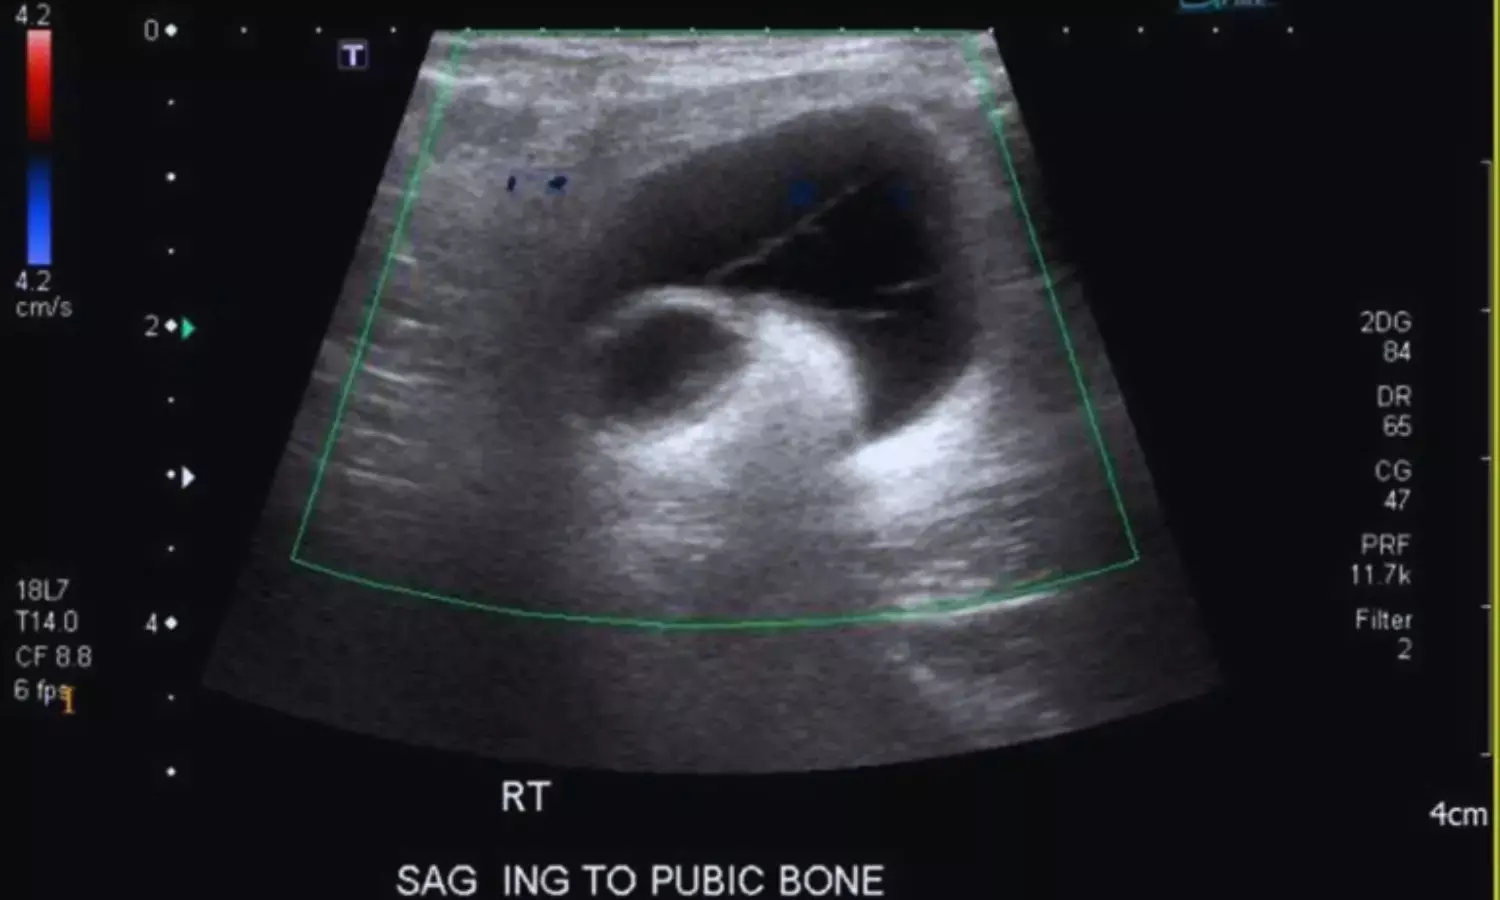

Ultrasound examination played a pivotal role in the diagnostic process. Imaging revealed a highly echogenic, irregular, folded structure with posterior acoustic shadowing, consistent with a meshoma. The lesion was located within the superficial subcutaneous tissue and was surrounded by inflammatory changes, including a fluid rim and a fibrous capsule. Notably, a thin tract extending from the meshoma to the skin surface was identified, suggestive of a cutaneous fistula. Increased vascularity around the lesion on Doppler imaging further supported active inflammation.

Based on these findings, a diagnosis of infected meshoma with cutaneous fistulization was made. Although the patient initially responded to intravenous antibiotics, with resolution of fever and normalization of inflammatory markers, the persistent painful mass necessitated surgical intervention. During surgery, dense adhesions and purulent material were encountered around the mesh, confirming the diagnosis. Complete removal of the infected mesh along with the fistulous tract was performed.